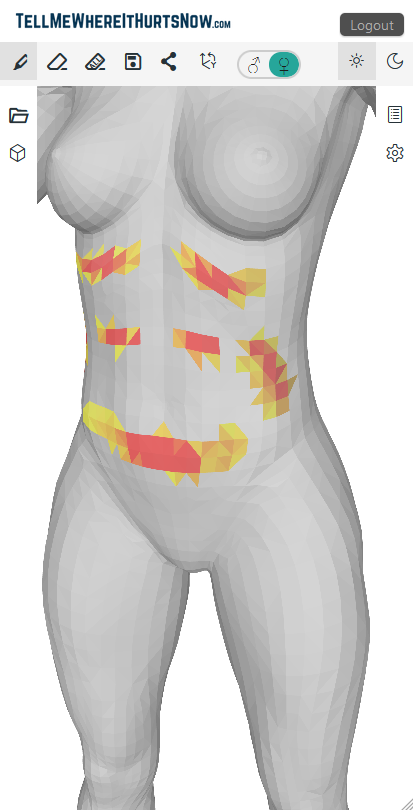

TellMeWhereItHurtsNow: Web app for visual pain communication. Mark areas on 3D body model, show intensity, share with doctors. Track pain over time. Works on all devices. Show doctors exactly where it hurts to improve communication and understanding.